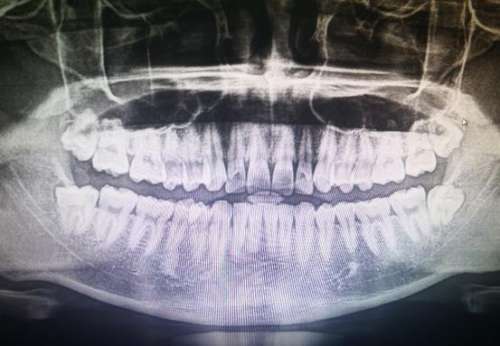

后槽牙爛了個大窟窿要不要拔?

后槽牙縫大是一種常見的口腔問題,常常會導致牙齒難以清潔,進而引起齲齒等不良結果。如果不及時修復,后槽牙縫大可能會導致牙齒疼痛,甚至會引起感染和失去牙齒。因此,對于縫隙較大的后槽牙,我們應考慮合適的修復方案。